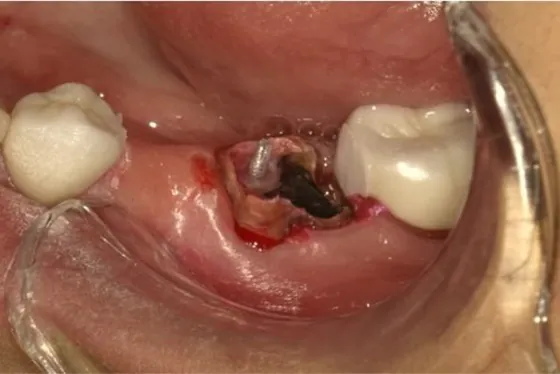

抜歯窩即時埋入症例

| 主訴 | 右上の奥の抜歯が必要な部分にインプラントをいれたい |

| 性別・年齢 | 女性・73歳 |

| 治療方法 | 抜歯窩即時埋入・インプラント埋入・パラFMCセット |

| 治療期間 |

9か月 |

| 費用 | 438,900円 |